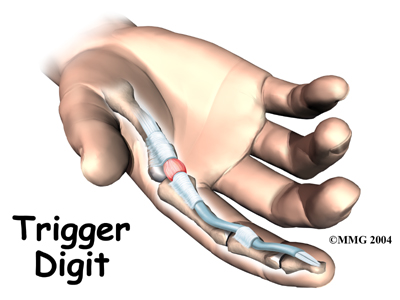

Trigger Finger and Trigger Thumb

Trigger finger and trigger thumb are conditions affecting the movement of the tendons as they bend the fingers or thumb toward the palm of the hand. This movement is called flexion.